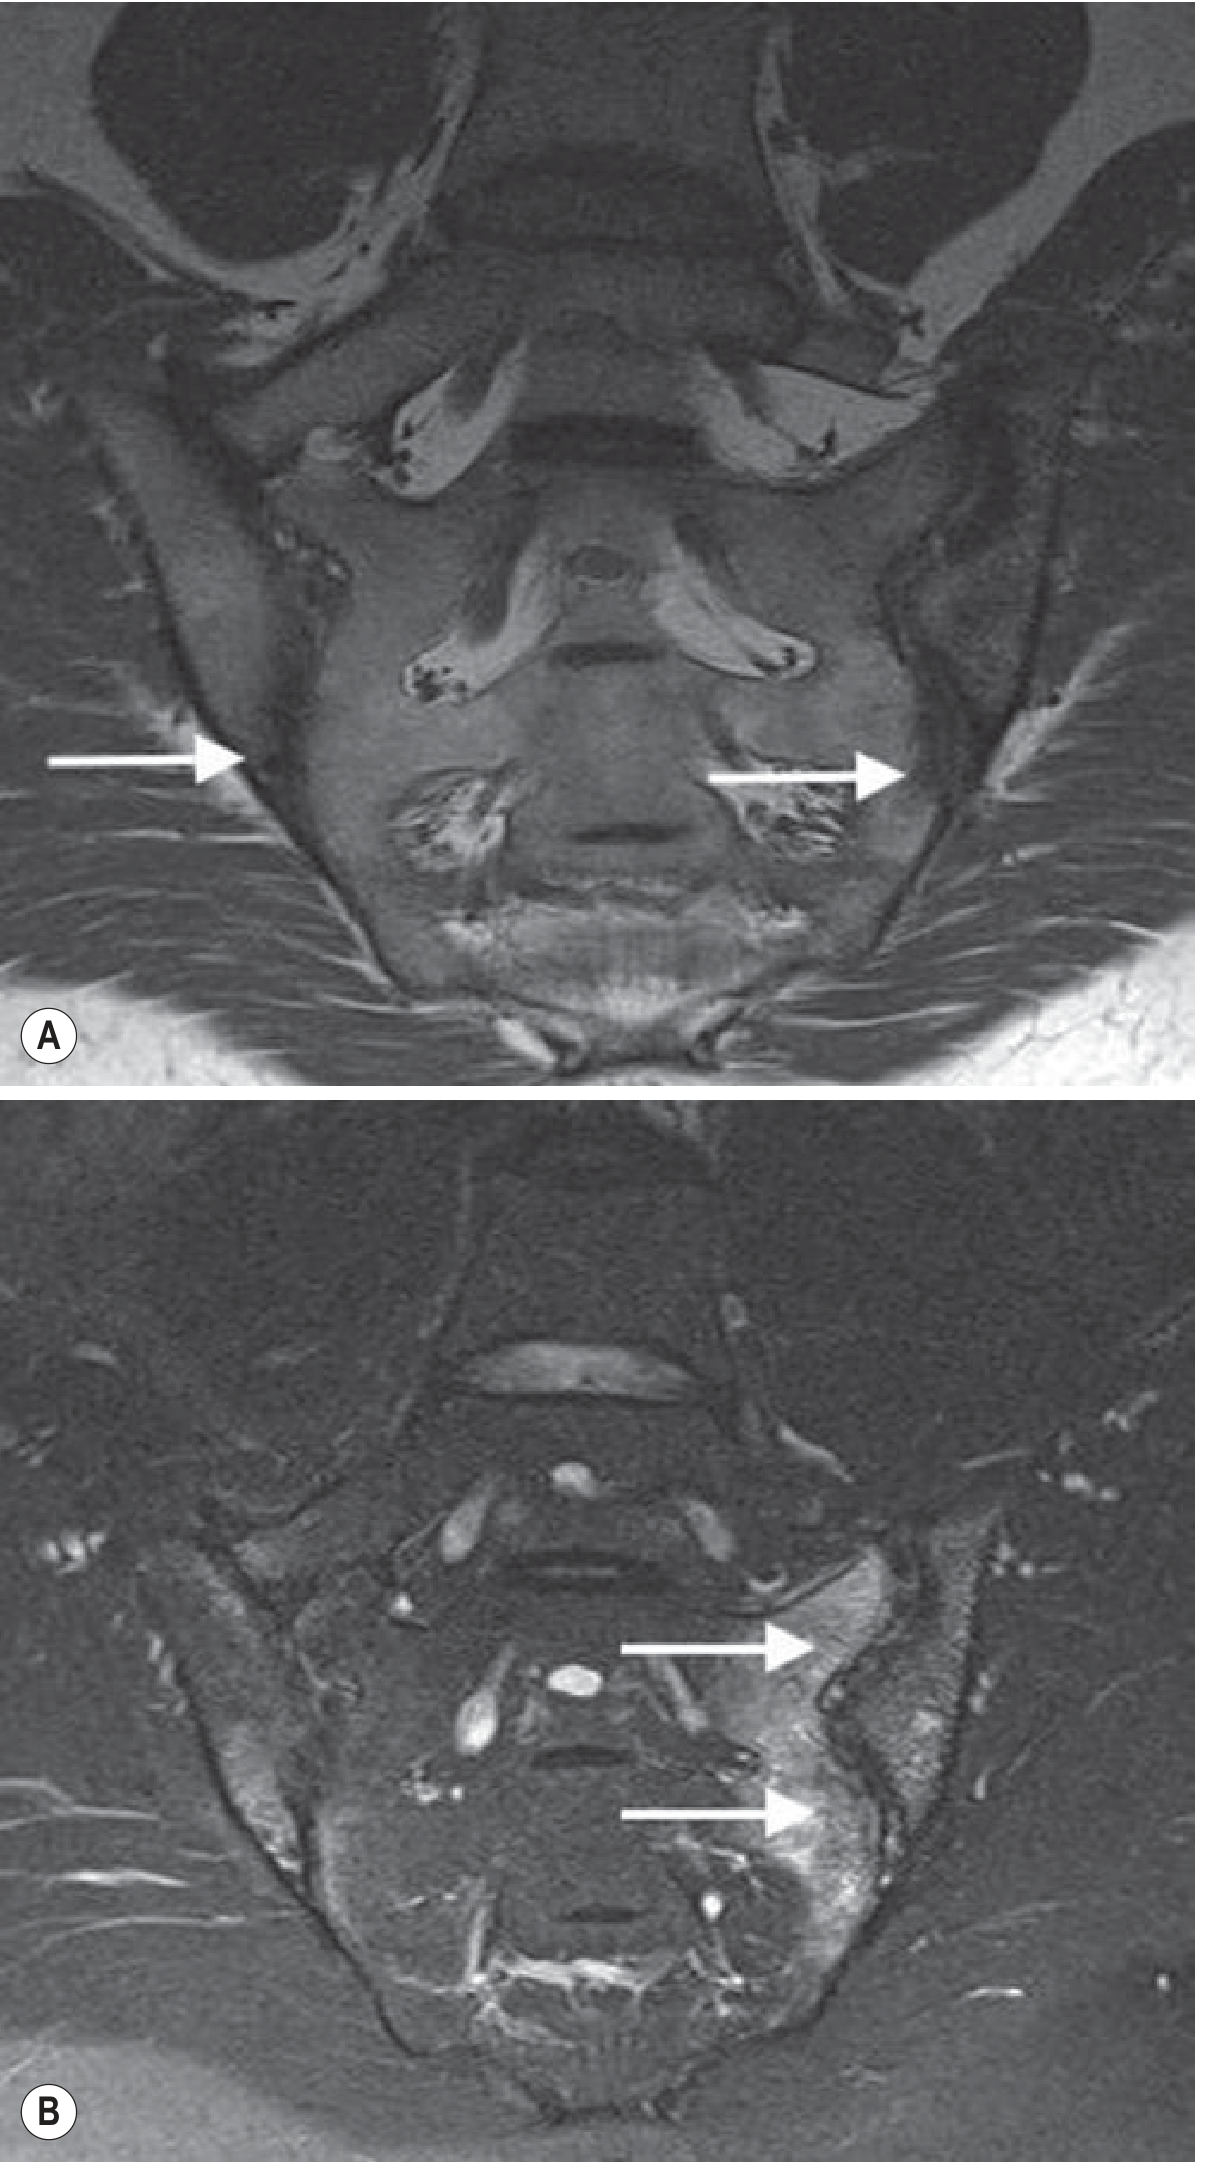

MRI of Sacroiliac Joints in AS:

MRI Sacroiliac Joints in AS — T1 showing erosions (A), T2 fat-suppressed showing subchondral oedema (B)

Fig. MRI of the sacroiliac joints: T1 (A) shows erosions with joint space loss; T2 fat-suppressed (B) shows extensive subchondral oedema — indicative of disease activity. — Grainger & Allison's Diagnostic Radiology